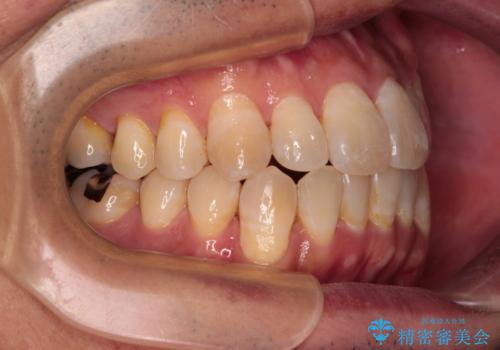

- 前歯のデコボコとクロスバイトを気にして来院された患者様です。

40代半ばであり、あまり周りに気を遣われずに治療を進めたいとのことで、インビザラインにて矯正治療を行うこととしました。

毎日22時間の装着時間をきっちりと守ってくださり、1年半かけずに思い通りの歯列に仕上げることができました。